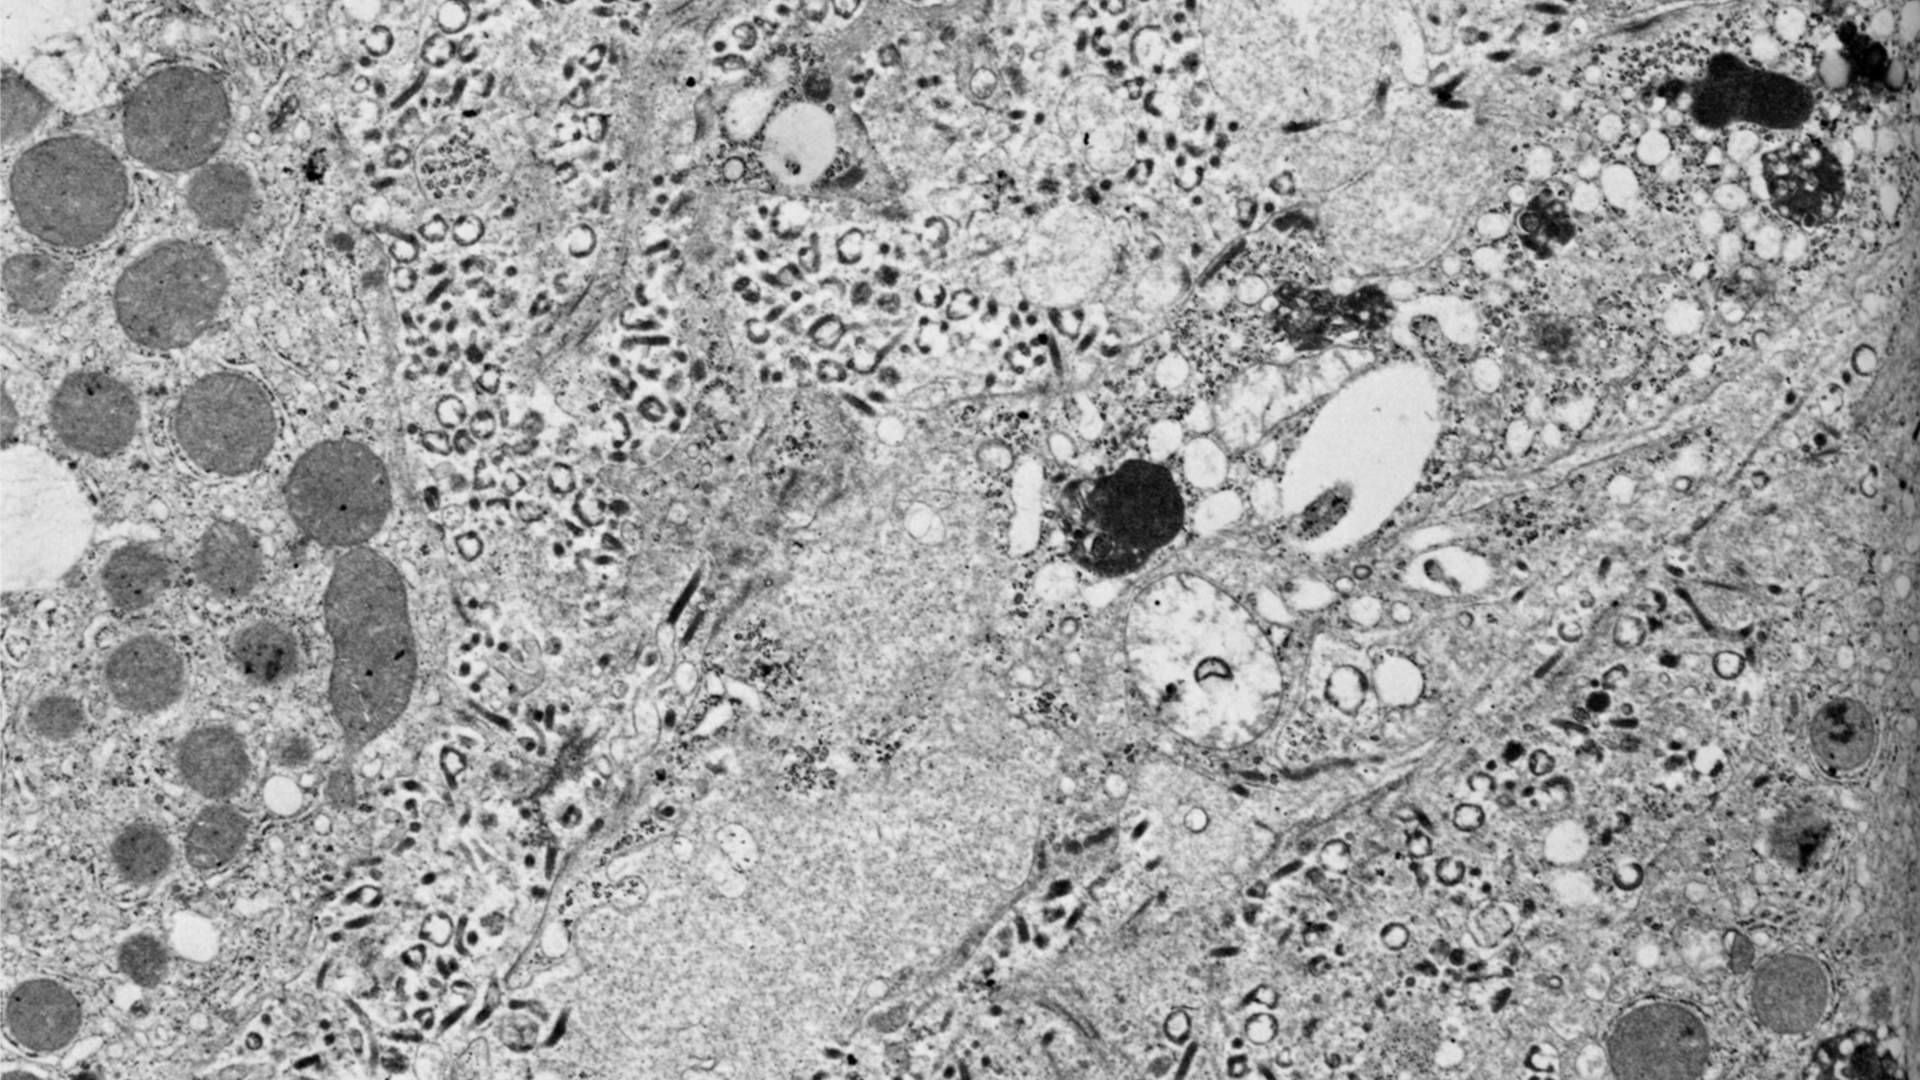

Marburg is transmitted to people from fruit bats and spreads among humans through direct contact with the bodily fluids of infected people, surfaces and materials. Illness begins abruptly, with high fever, severe headache and malaise. Many patients develop severe hemorrhagic signs within seven days. Case fatality rates have varied from 24% to 88% in past outbreaks depending on virus strain and case management.